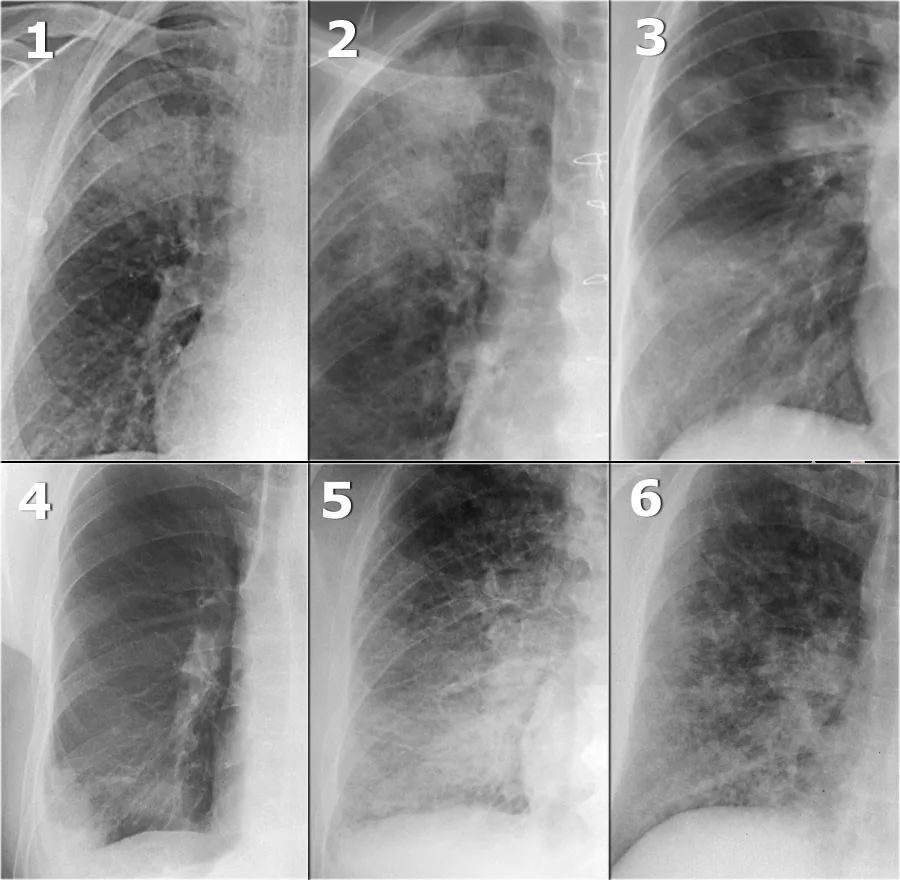

教科书上也很少见这么经典的胸片附肺实变的轮廓征图

胸部x线肺部病变一实变

来看一下在胸片上如何辨别不同肺叶的不张以及肺不张与肺实变的鉴别

絮状,模糊,斑片状气腔病变,通常位于中心.01肺泡性肺水肿

肺实变

肺炎胸片

肺实变x线表现图片